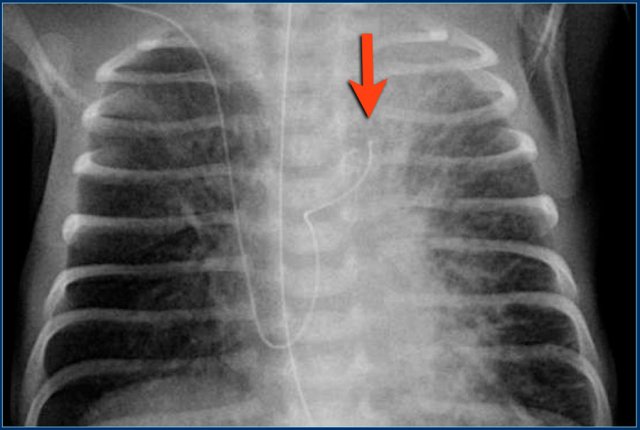

1. Deep position of umbilical artery line, in aortic arch.

2. Umbilical vein line with tip in right portal vein.